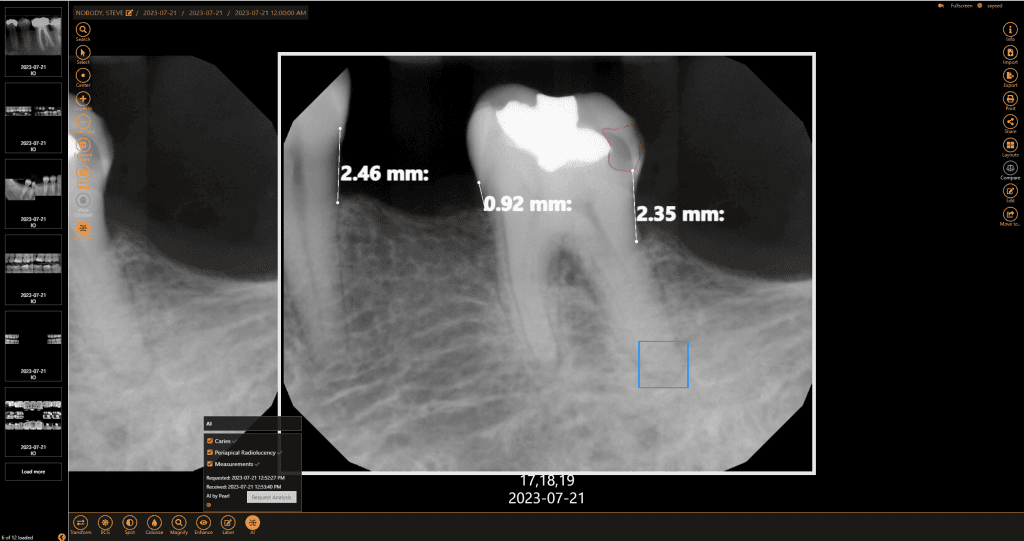

Get a second opinion to quickly detect decay, identify tartar buildup, and assess bone levels, ensuring a more accurate diagnosis of periodontal disease.

Speed up diagnosis and treatment planning with fast initial screenings and real-time AI feedback, giving you confidence in chairside decisions.

Within minutes, have more data than ever to guide and support your diagnosis with the patient chairside. AI makes it easier to visualize the areas of concern so patients can make a more informed decision.

Submit claims with greater confidence when the diagnosis is supported by quantified data.